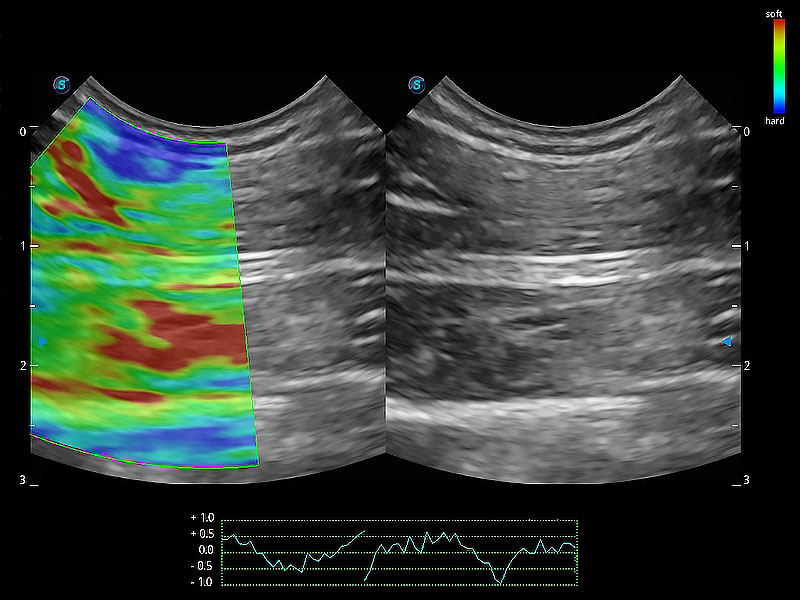

• 应变式弹性成像

操作简便,无需高频度外力作用即可真实反映组织的形变,快速评估肿瘤良恶性。

ProPet 80 全新的动物超声智能软件和丰富的探头群,为动物医生提供了高清晰度和精细分辨率的图像,无论在宠物、马科、畜牧还是实验室动物等应用中都可以轻松应对,为您的日常工作带来满意的体验。

(犬)肠道